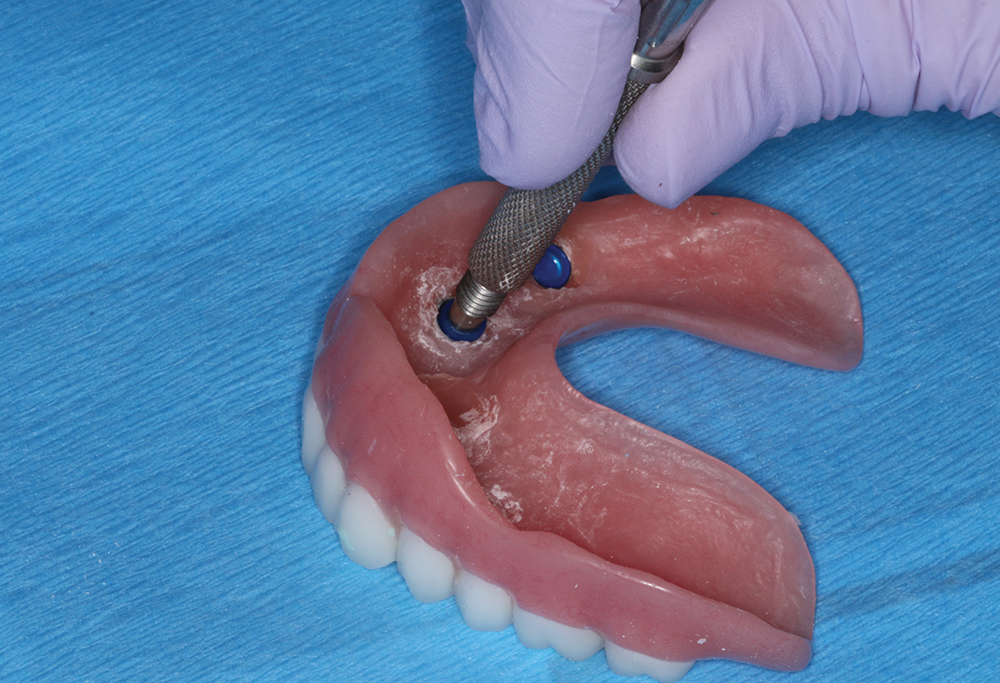

CHAIRSIDE PICKUP OF LOCATOR HOUSINGS

with Len Conner, CDT

Director of Education and Clinical Affairs at Zest Dental Solutions

In the standard protocol for the Locator Overdenture, the Locator housings are processed into the overdenture by the dental lab. However, some doctors may prefer to pick up the Locator housings intraorally. The following presentation, courtesy of Len Conner, CDT, director of education and clinical affairs at Zest Dental Solutions, illustrates the straightforward clinical procedure for intraoral pickup.